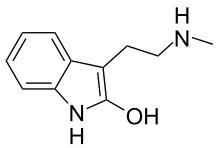

| 2-HO-NMT | Plants | 2-OH | H | CH3 | 2-hydroxy-N-methyltryptamine | 106987-89-7 |